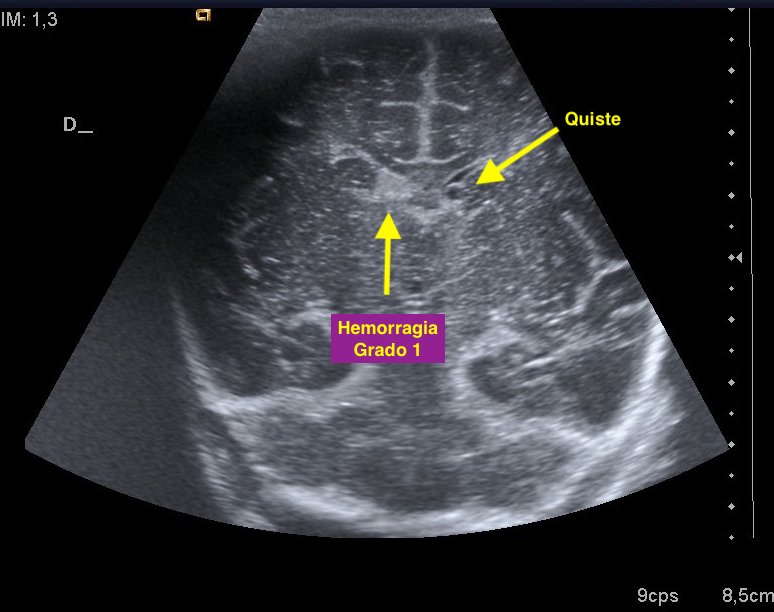

293. Hemorragia Matriz Germinal Grado 1.

Uno de los lugares más especiales para hacer ecografía es en los servicios de neonatología. Hacer una ecografía transfontanelar a un recién nacido es una experiencia inolvidable, es de las pruebas a las que uno le pone siempre especial cariño. Particularmente a mi, me superencanta. Hoy quería subir este caso, muy sencillo. Muy bonito. Me acuerdo de ella, era muy linda.

En el caso de esta pequeña nos pidieron una ecografía de control de una hemorragia de la matriz germinal grado 1 diagnosticada a las pocas horas de nacer.

En el Post 213 ya hable de este particular, pero hoy revisando casos y casos que tengo almacenados, he pasado todos la tarde en este empeño, me he encontrado con este caso, me acuerdo de ella. La hice yo en la unidad, inolvidable.

La hemorragia es la imagen hiperecogénica, homogénea y psudoredondeada del lado derecho. El quiste, redondo e hipoecogénico, del lado izquierdo. No se pudo demostrar una hemorragia en ese lugar.

1

Pequeña hemorragia matriz germinal lado derecho, grado uno, y pequeño quiste asociado izquierdo indicando reabsorción parcial en ese lugar. Imagen 1.Sistema ventricular de tamaño normal. Imagen 1 a 4.

El índice de resistencia vascular se encontraba en los márgenes normales. Imagen 5.